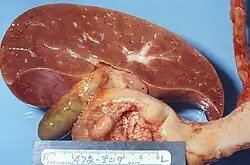

![]() Preparat sekcyjny wątroby pacjenta z zespołem Reye’a. Na przekroju narządu widać charakterystyczną bladość wywołaną nagromadzeniem lipidów w hepatocytach | |